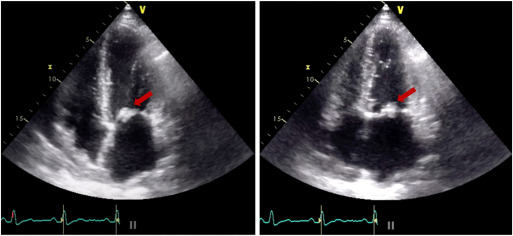

diagnose and guide the management of a patient with complex, multivalvular heart disease, you simply must read XXX from Bravo et al. Their 45yo patient with antiphospholipid syndrome had a series of complications including a stroke and unprovoked pulmonary embolism, non-bacterial thrombotic endocarditis, valve surgery and valve thrombosis. Through their careful, intermittent assessment with 2D and 3D TTE and TEE as well as cardiac CT imaging, they were able to strategize subsequent care including mitral valve replacement. Later in this patient’s clinical course, echo-guided, low-dose thrombolysis helped to safely resolve a stenotic MVR with clot-burden. They include outstanding 3D TEE, CCT, and surgical images for you.”